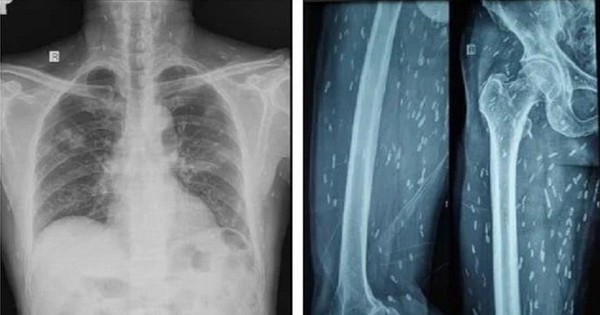

Trên kết quả X-quang và CT-Scan toàn thân, bác sĩ phát hiện bệnh nhân có vô số nang sán dải còn sống hoặc đã bị vôi hóa ở não, nhu mô phổi, trong da, cơ trên toàn bộ cơ thể. Qua điều tra dịch tễ, bác sĩ ghi nhận bệnh nhân có thói quen hay ăn gỏi thịt lợn tái sống và uống nước không đun sôi trong nhiều năm.

Sán làm tổ chi chít khắp cơ thể vì món khoái khẩu nhiều người Việt 'nghiện' - Ảnh 2.

Ấu trùng nang sán dải lợn ký sinh khắp cơ thể người bệnh được phát hiện trên kết quả kiểm tra hình ảnh